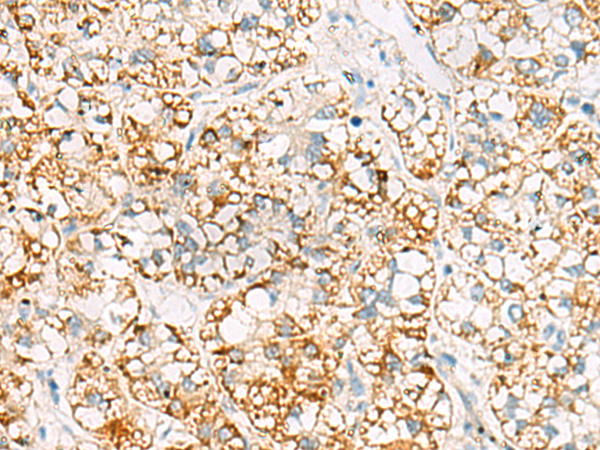

分类: 科研抗体货号: P09794别名: HK2应用: WB,IHC反应种属: Human, Mouse